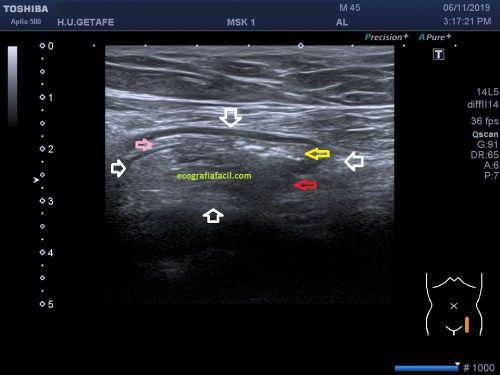

Vamos a partir de la normalidad y te vienes a ver ahora la patología que hoy nos ocupa, mira. En ocasiones podemos encontrarnos la imagen patológica que indica luxación del tendón, imagen 2. Es un corte en Eje corto. Ves la corredera bicipital vacía, el tendón fuera de su localización habitual, hacia medial, como es habitual, pero conservando la ecoestructura.

Efectivamente, verás que bordeando el tendón existe una mínima cantidad de líquido que está envolviendo u ocupando la vaina del tendón, se ve anecoico y efectivamente es cierto, si lo has visto, enhorabuena, a parte de la luxación, esa es la otra semiología evidente que podemos ver en la imagen 2.